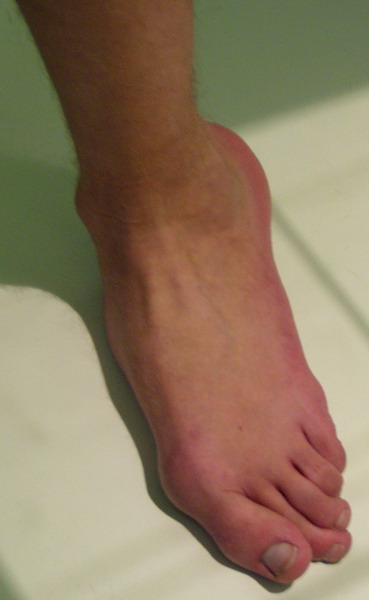

Пациент 15 л., болезнь Литтля, спастический нижний парапарез, интеллект высокий. Ребенок настроен на активный образ жизни. С недавнего времени начал ходить без дополнительной опоры. Появилась проблема с левой стопой - во время ходьбы опора приходится на смещенную кнутри таранную кость.

Может образоваться болезненный натоптыш или язва.Общепринятой операцией является трехсуставной артроде с мобилизацией таранной кости. Выполнять такую операцию у спастика и в раннем возрасте проблематично. Родстьвенники тем более готовы материально и морально осуществить хирургическое лечение за рубежом, если оно показано и возможно.Предпочтительно в Австрии и Германии. Если кто-то посоветует координаты таких клиник - были бы признательны.